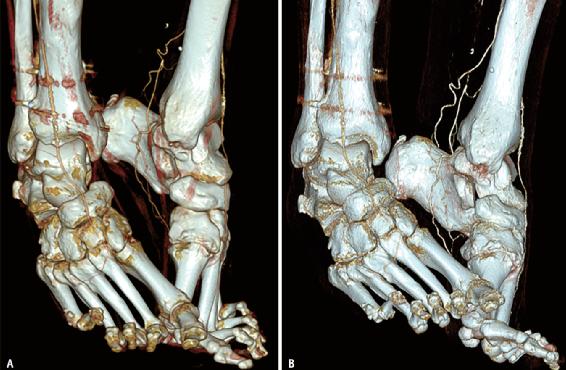

图9 69岁女性,患有已知外周动脉疾病。A、B 从使用145ml碘造影剂的能量积分探测器CT血管造影(A)三维重建图像看起来类似于仅使用55ml相同碘造影药的PCD-CT血管造影图像(B)。该示例说明了利用来自PCD-CT的改善的碘信号来减少碘造影剂需求的能力。

与肌肉骨骼成像相关的多能量CT重建包括评估痛风(图10)和骨水肿的虚拟去钙图像。致密的皮质骨和小梁使骨的髓腔成为CT评估的一个挑战性部位。例如,与创伤性损伤相关的骨水肿和骨髓瘤的局灶性髓样病变通常使用常规CT图像模糊。来自多能量采集的虚拟去钙重建允许放射科医生清楚地可视化髓腔,以识别由于创伤或肿瘤引起的骨髓水肿,并且可以使用类似于双能量CT创建的PCD创建。

图10 36岁男性,患有痛风性关节炎。A-D 使用PCD-CT和随后的材料分类获得的图像显示,第一趾间关节处绿色的尿酸单钠沉积。

与双源双能CT系统不同,PCD不限制多能量应用的扫描视野,将多能量CT成像的优势扩展到更大的患者。虽然PCD将随着新软件版本的发展而发展,新软件版本旨在允许多能量数据的可视化和定量显示,但PCD-CT多能量功能将“始终开启”并处于全视野,例如,允许在一次扫描中显示足部骨折,同时显示骨髓水肿和痛风,但每个成像任务需要多次重建。最后,改进的碘信号、基于多能量的区分和材料分离的组合可有助于扩大定量任务的临床潜力,用于局部病变(例如,区分肾囊肿和实体肾肿块中的碘)或实质器官,如肝脂肪定量。需要进一步研究以确定PCD-CT在这些临床环境中的临床应用。